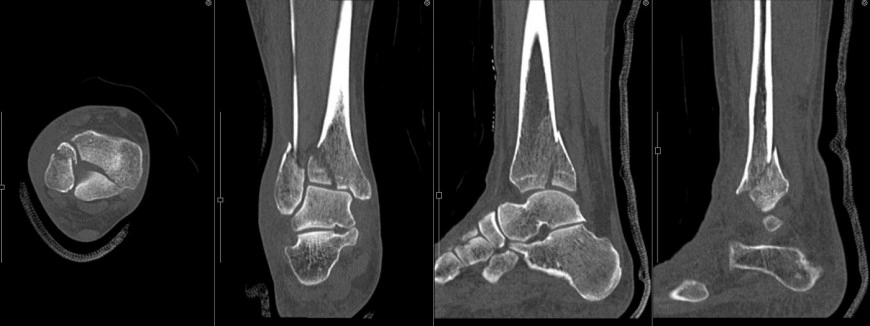

現在は、コンピュータの進歩によりとても細かな輪切りの画像を取得できることから三次元(3D)画像や任意の断面(MPR:multi-planar reconstruction)の画像を作成することが可能です。これらの画像を用いて病変の部位を詳しく診断したり、手術の計画を立てたり、患者様へのご説明を行っております。

膝関節 立体像

膝関節 断面像